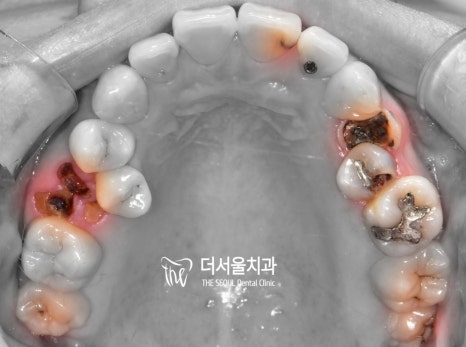

상, 하악 초진 사진입니다.

한눈에 봐도 썩은 곳들이 많네요.

그중에서는 더는 자연치를 살릴 수 없을 정도로

심각한 상태인 치아들이 많았는데요.

위 사진에서 볼 수 있듯이

약간 뻐드러진 치아 배열과 우식,

그리고 제위치에서 벗어난 소구치 때문에

여러 고민이 많으셨던 분인데요.

이분께서는 교정과 우식 제거를

동시에 원하고 계셨던 상태였습니다.

따라서 더 서울에서는 충치치료 먼저 진행한 뒤,

치열 개선을 시작하는 방법으로 돕기로 했는데요.